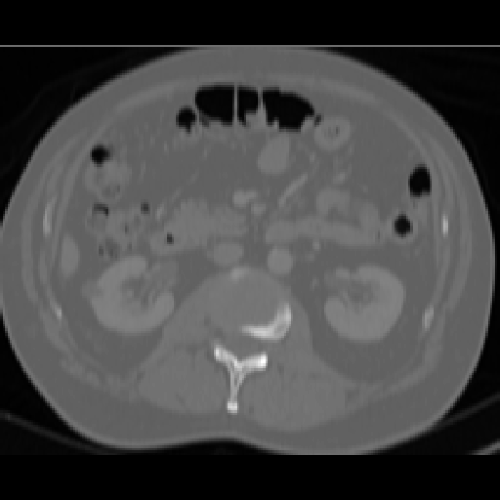

The segmentation task is to obtain the organ labels corresponding to the voxels. We used a 3mm grid to query BodyGPS coordinate estimations. Once the coordinates are known, the atlas mask is used to determine the label. Transferring all labels back to the source image will construct a segmentation map. In an interactive mode, one could query mouse location in real time to get organ labels that will serve as a classifier.

The computational time for full volume is slow, on the order of minutes. However, any grid sampling could be used to change the trade-off between speed and accuracy without changing the model. A single query takes less than 1ms. A qualitative example is demonstrated in Figure 2.

Refer to caption

(a) Input Image

(b) BodyGPS Estimate

(c) Ground Truth Mask

Figure 2: Application of BodyGPS on segmentation